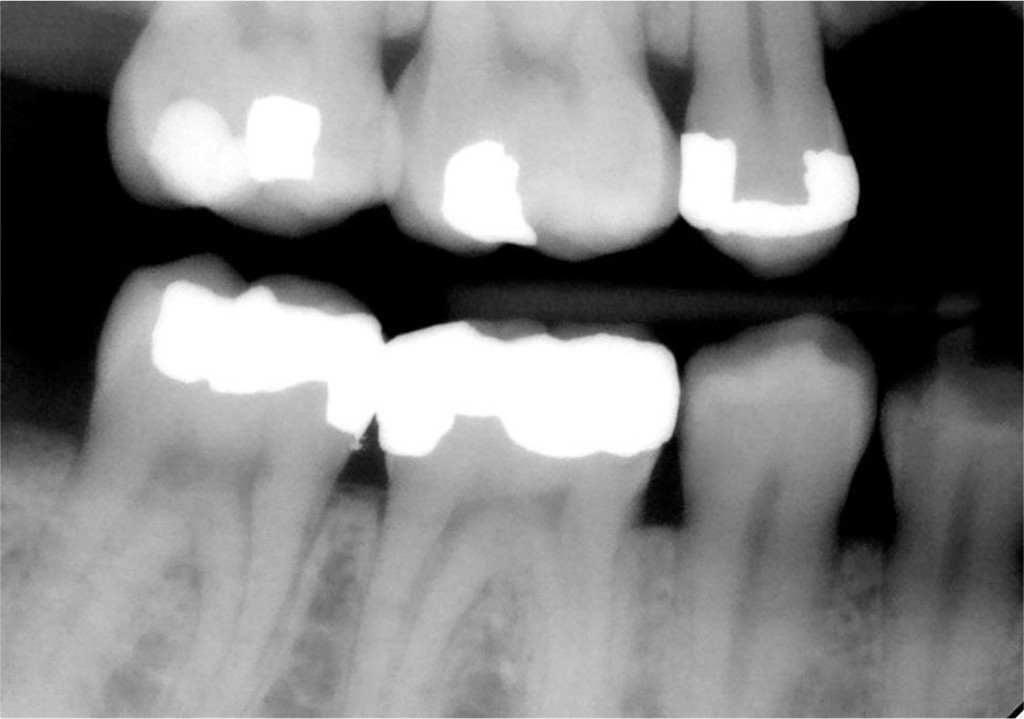

11. On which surface a recurrent caries can be detected?

12 / 35

12. On which surface a recurrent caries can be detected?

Mesial 4.7 is normal proximal caries not recurrent, distal 4.6 is recurrent , mesial 4.6 and distal 4.5 are open margin